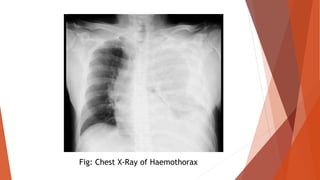

 Investigation specific for cause: Ultrasound abdomen, Doppler study in

vascular injury and often angiogram, chest X-ray in hemothorax, CT scan in

major injuries, CT head in head injuries.

Fig: Chest X-Ray of Haemothorax

MEASUREMENT OF BLOODLOSS  Clot size of a clenched fist is 500 ml.  Blood loss in a closed tibial fracture is 500-1500 ml in a fracture femur is 500- 2000 ml.  Weighing the swab before and after use is an important method of on table assessment of blood loss.  Hb% and PCV estimation.  Blood volume estimation.  Measurement of CVP or PCWP.  Investigation specific for cause: Ultrasound abdomen, Doppler study in vascular injury and often angiogram, chest X-ray in hemothorax, CT scan in major injuries, CT head in head injuries.

Fig: Chest X-Rayof Haemothorax